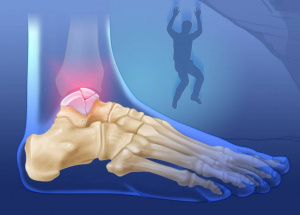

таранной кости

Удивительные секреты анатомии таранной кости: почему эта небольшая косточка так важна для нашего движущегося мира Когда мы задумываемся о том, как устроено

Анатомия таранной кости: секреты строения и функции этой важнейшей части стопы Когда мы говорим о нашей способности двигаться, удерживать равновесие и

Анатомия таранной кости: ключ к пониманию строения стопы и ее функции Когда мы задумываемся о здоровье нашей стопы, зачастую вспоминаем о костях, мышцах

Анатомия таранной кости: ключ к пониманию строения и функций стопы Когда мы задумываемся о здоровье наших стоп, особенно о таких сложных и важных структурах

Анатомия таранной кости: ключ к пониманию стопы и её функций Когда мы говорим о здоровье и функциональности человеческой стопы, одна из самых важных составляющих

Анатомия таранной кости: ключ к пониманию анатомии стопы и ее функций Когда мы задумываемся о здоровье наших ног, особенно о таких сложных структурах

Анатомия Таранной Кости: Всё, что Нужно Знать о Незаменимом Элементе Стопы Когда мы задумываемся о здоровье наших ног, обычно обращаем внимание на такие

Анатомия суставных поверхностей таранной кости: все, что нужно знать о структуре и функциях Когда речь заходит о строении стопы и её двигательной функции